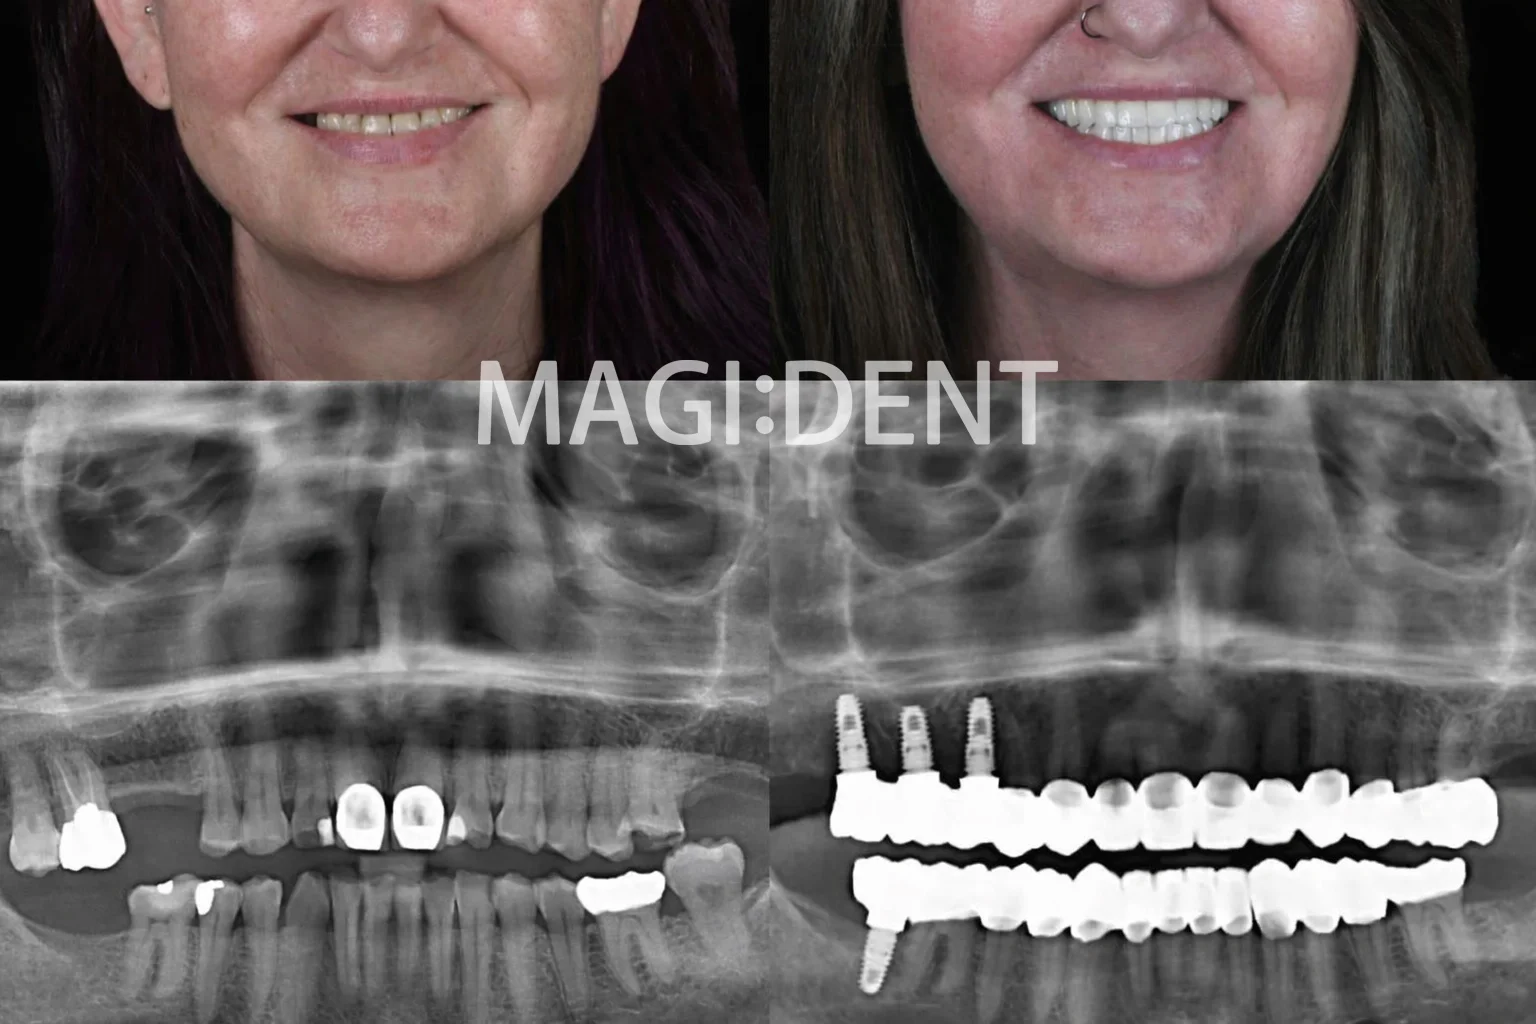

Dentalni implantati se često predstavljaju kao “trajna” zamjena za zub. I istina je da mogu trajati jako dugo — ali nisu magija. Najrealniji odgovor na pitanje koliko traju dentalni implantati glasi: zavisi od više faktora, a najviše od desni, higijene i navika nakon ugradnje.

Važno je razumjeti jednu stvar odmah na početku: implantat nije samo “šraf u kosti”. To je sistem koji uključuje implantat (u kosti), nastavak (abutment) i krunicu. Ti dijelovi ne stare jednako, pa je normalno da se tokom života ponekad zamijeni krunica, dok implantat u kosti može ostati stabilan decenijama.

Implantat vs krunica: šta se “troši” kroz godine

Jedna od najčešćih zabluda je da je implantat isto što i krunica. U realnosti:

• Implantat (u kosti) je “osnova” i obično traje najduže.

• Krunica je dio koji najčešće zahtijeva zamjenu nakon godina, jer trpi žvakanje, navike (npr. grickanje) i trošenje.

Zato je dugotrajnost implantata često kombinacija: stabilan implantat + povremeno održavanje i eventualna zamjena potrošnih dijelova.

Koliko traju dentalni implantati u praksi najviše zavisi od tri stvari: zdravlja desni, higijene i opterećenja (navika poput bruksizma i pušenja). Implantat u kosti može trajati veoma dugo, dok se krunica ponekad mijenja kroz godine, što je normalan dio održavanja. Najbolji rezultat dobijate kada implantat tretirate kao “investiciju”: redovno čišćenje, kontrole i pametne navike vraćaju se kroz stabilnost i sigurnost osmijeha.